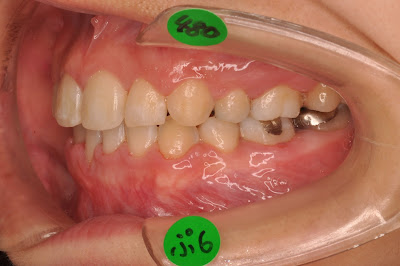

典型的な乱ぐい歯〔叢生症例です)

前歯の何本かが逆の噛み合せになって

噛むときにロックされます。

これでは食事で噛む時に下顎が自由に動きません。

下の前歯が逆になって上の歯から打撃を受け歯ぐきが下がっています

このままでは歯の寿命もあまりないでしょう